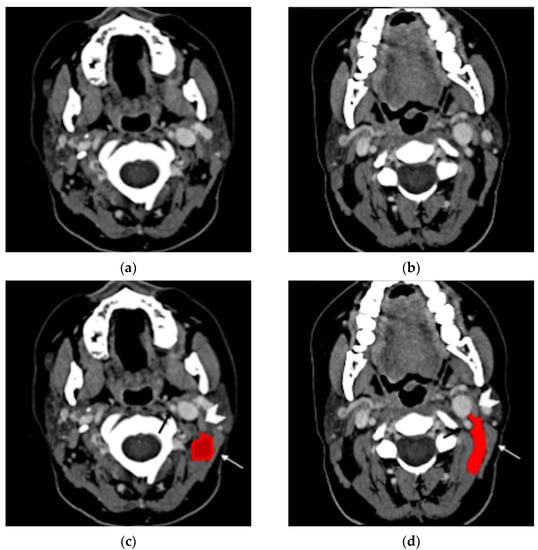

Contrast-enhanced neck CT aims at demonstrating and precisely defining the anatomical limits of the neck abscess that appears as a low-attenuation collection with typical rim enhancement (Figure 4) and surrounding soft tissue oedema. Neck CT should be reconstructed with 2–3 mm thick slices and a soft tissue kernel and window. The suppurative collection is usually located under the sternocleidomastoid muscle, in the posterior-cervical or perivertebral spaces, but extensions into the retropharyngeal space [30,51], parapharyngeal space [30,42,45,53], or even into the thorax [24,26,46,54] have been described, coherently with neck fascial anatomy and least resistance pathways.

Figure 5. Thirty-year-old woman with oculo-auricular-vertebral spectrum. Contrast-enhanced axial CT (a) shows hypodense left neck abscess in the parapharyngeal and pharyngeal mucosal spaces, with minor involvement of the visceral and posterior cervical space (dotted rectangle). Note the peripheral enhancement and the soft tissue oedema. Axial CT with bone kernel (b) shows hypodense cholesteatoma eroding the os tympanicum (black arrow) as the origin of the neck abscess. Coronal T2w MRI (c) shows an hyperintense neck collection (white arrow) medial to the sternocleidomastoid muscle (white arrowhead). The patient proved to have a Bezold’s abscess associated with an os tympanicum cholesteatoma.